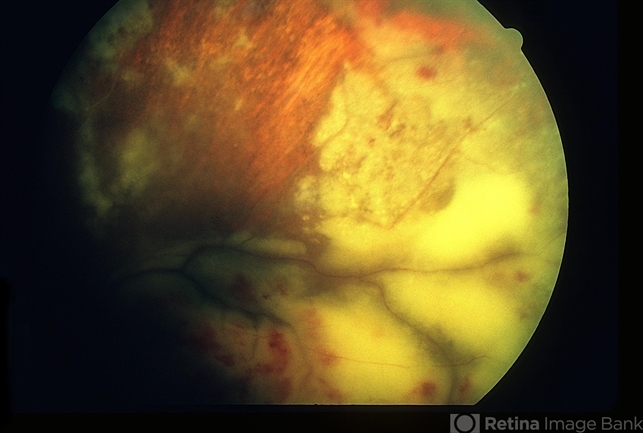

- Extensive peripheral retinitis and hemorrhagic foci in a patient with Wegner's granulomatosis.